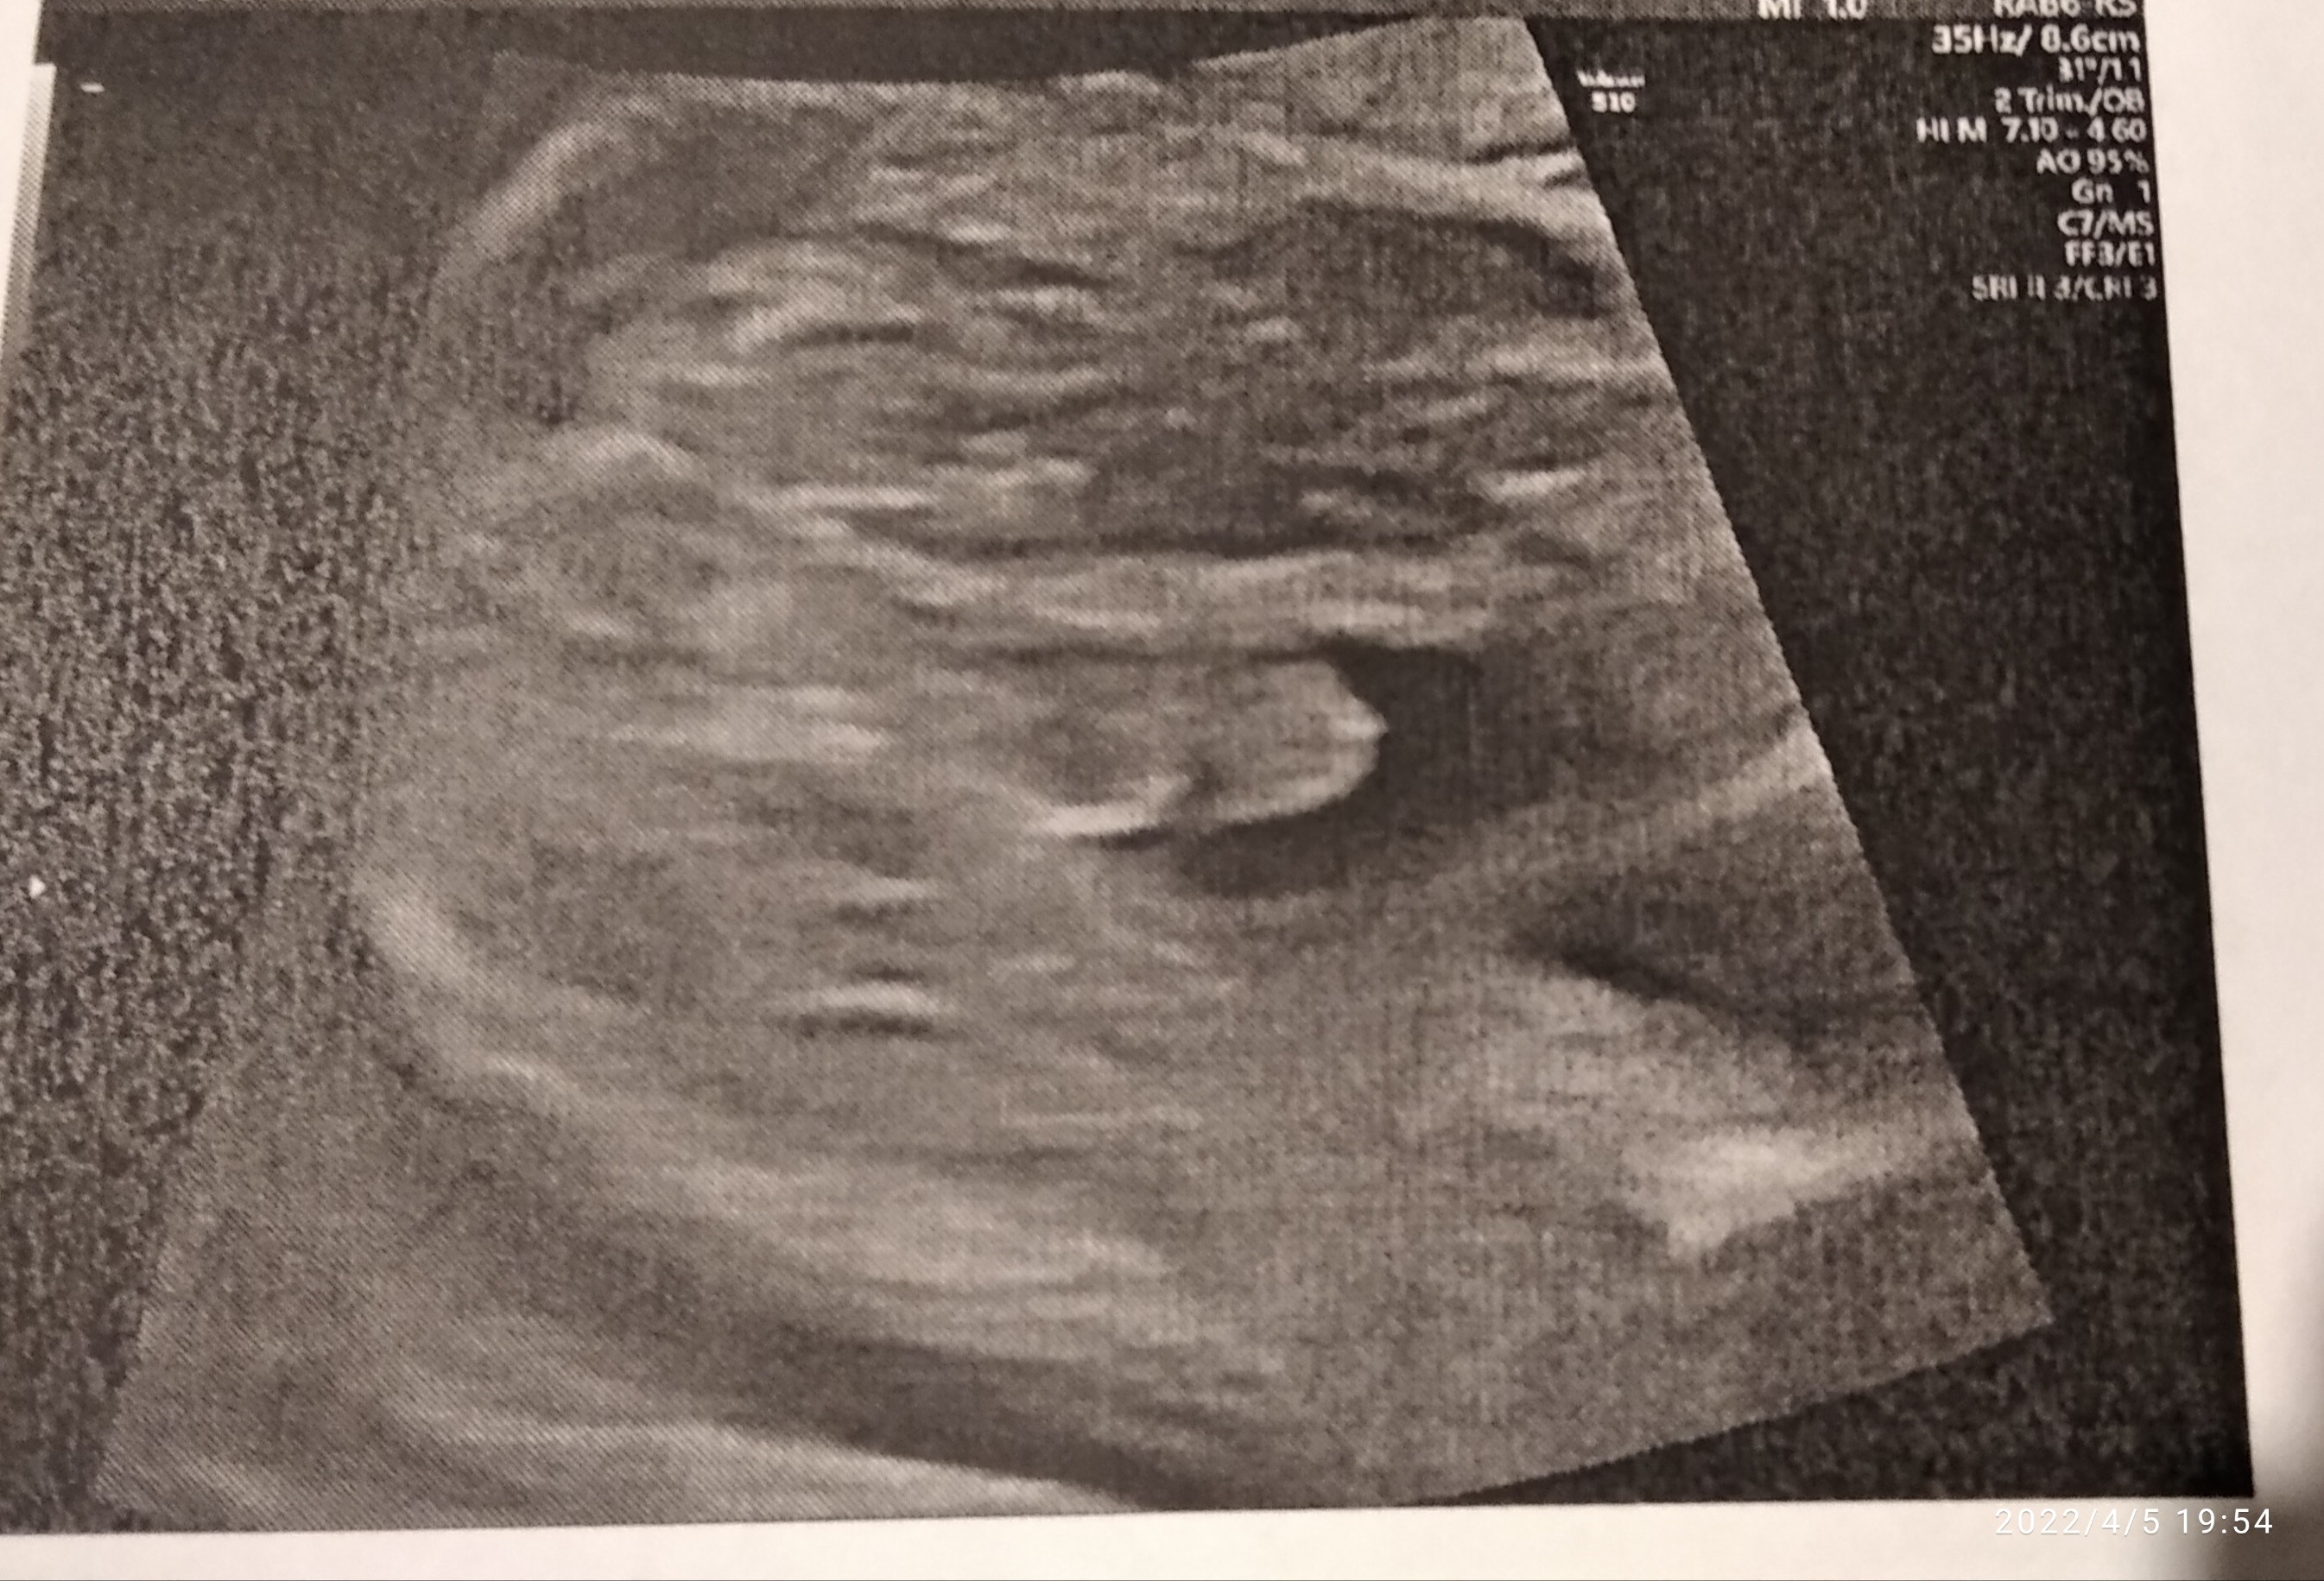

Tydzień ciąży, co widzicie drogie Panie chłopca czy dziewczynkę?

Wydaje mi się, że wygląda to w ten sposób jak zaznaczyłam na zdjęciu niżej. Może są tutaj bardziej doświadczone mamy niż ja i się wypowiedzą. Jedną córkę mam, teraz fajnie by było mieć chłopca ☺

Ok, No zobaczymy co się urodzi za ok 8 tygodni. Zastanawia mnie ta ciemna kropka w kroku.Witam, według mnie dziewczynka.

Nie mam innego zdjęcia, lekarz stwierdził ze chłopiec. Ze ta cześć koło dupki to worek mosznowy. No ale ta kropka mnie zastanawia No i nie widzę wystającego penisa. Ważne żeby się urodziło zdrowe. Synek czy dziewczynka bez różnicy.Też mnie to zastanawia, może masz inne zdjęcie? Lekarz nic nie mówił?